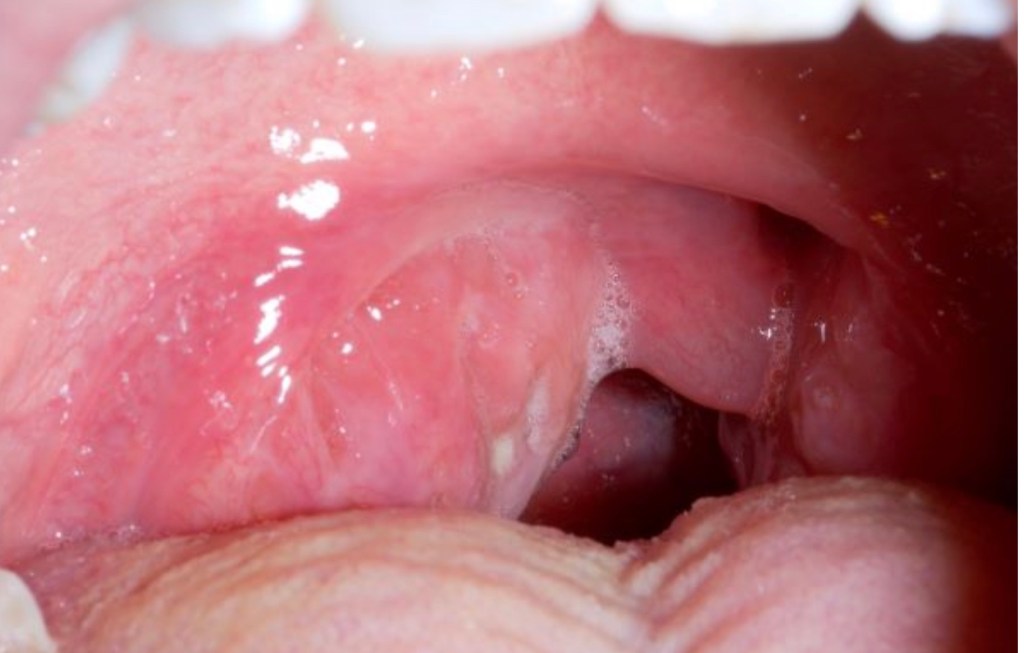

3. Peri-tonsillar abscess (Quinsy)- when the infection spreads through the capsule of the tonsil, pus collects outsides the tonsil and displaces the tonsil inwards, nearly occluding the oral cavity.Peritonsillar abscess must be treated with antibiotics and may need a drainage procedure to remove the pus and to hasten